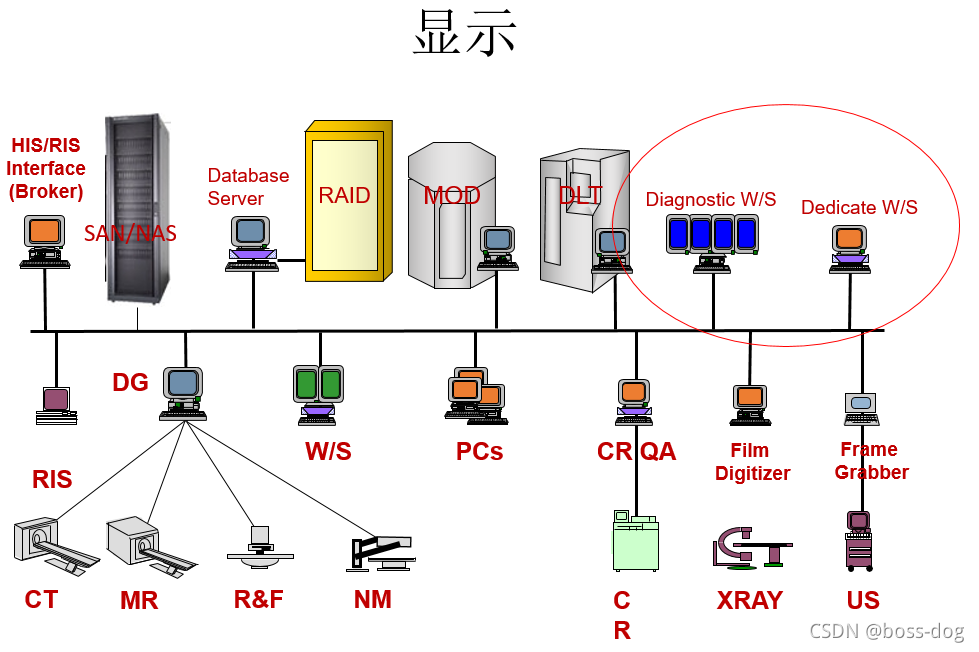

工作站(图片要分发到电脑前面,让医生来做诊断):

1.高等的:由专家(专门的医生或护士进行分析)用于高级诊断,比如基于三维图像绘制等等。

2.诊断:初步诊断,比如在阅览室通过片子进行分析等等。

3.临床:非影像科的医生,如泌尿科、骨科、急诊科的医生需要看着图片来指导他做手术,他们也需要工作站来显示这个图片。

4.在家里阅片:将图片能够传送到家里的笔记本电脑上,属于低端的基于电脑的显示器。